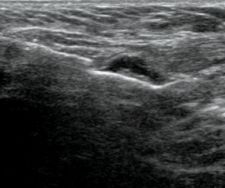

While the Celero can be used to biopsy masses in any part of the breast, I believe it is most useful in the biopsy of axillary lymph nodes. I recently had a case in which I biopsied an ill-defined (lobular carcinoma) mass within the breast using the Suros ATEC 9-gauge vacuum-assisted needle. Subsequent ultrasound of the axilla revealed a prominent lymph node on that side and rather than use the ATEC, I opted for the Celero. Those who prefer fine needle aspiration often believe that one should sample from multiple areas of a lymph node and avoid the vascular hilus. However, vacuum-assisted devices can make this difficult to achieve. With the Celero, I can easily sample from two or three areas within the same lymph node and clearly avoid the vascular regions. The Celero provides greater control, a smaller needle, and encompasses the best of both worlds — vacuum-assisted true cut technology with multiple insertions.

The Hologic device is one of a kind when it comes to sampling axillary lymph nodes. With the ability to pre-fire the inner cannula, I am able to control exactly where my needle goes, thereby ensuring a safe and comfortable experience for the patient.